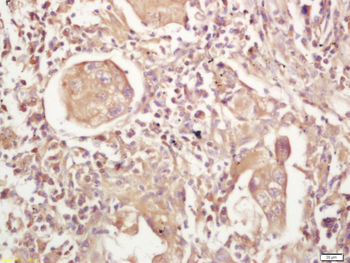

IF, IHC-Fr, IHC-P, WB

应用稀释比例:WB=1:500-2000, IHC-P=1:100-500, IHC-F=1:100-500, IF=1:100-500